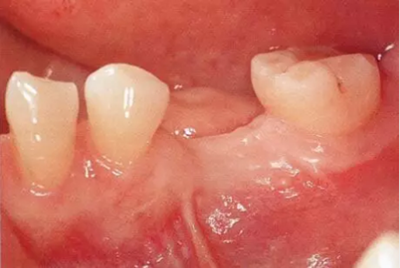

▲圖9-1

頰側和牙槽嵴幾乎沒有角化齦(Type3-Class1)

▲圖9-2,3

圖9-2 全損牙槽嵴的頂部,將牙齦移植片固定在頰側方向。待牙齦愈合后植入種植體。

圖9-3 牙齦愈合后的狀態(tài)。缺損牙槽嵴和頰側均獲得了角化齦。